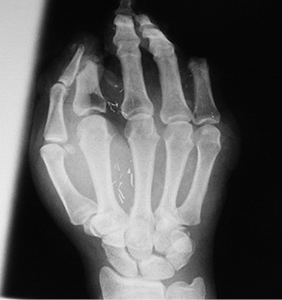

3 pav.

4 pav.

Priekinė ir šoninė kairės plaštakos rentgenograma. Stebimi II ir V pirštų kauliniai defektai per proksimalinį interfalanginį sąnarį (3 ir 4 pav.)